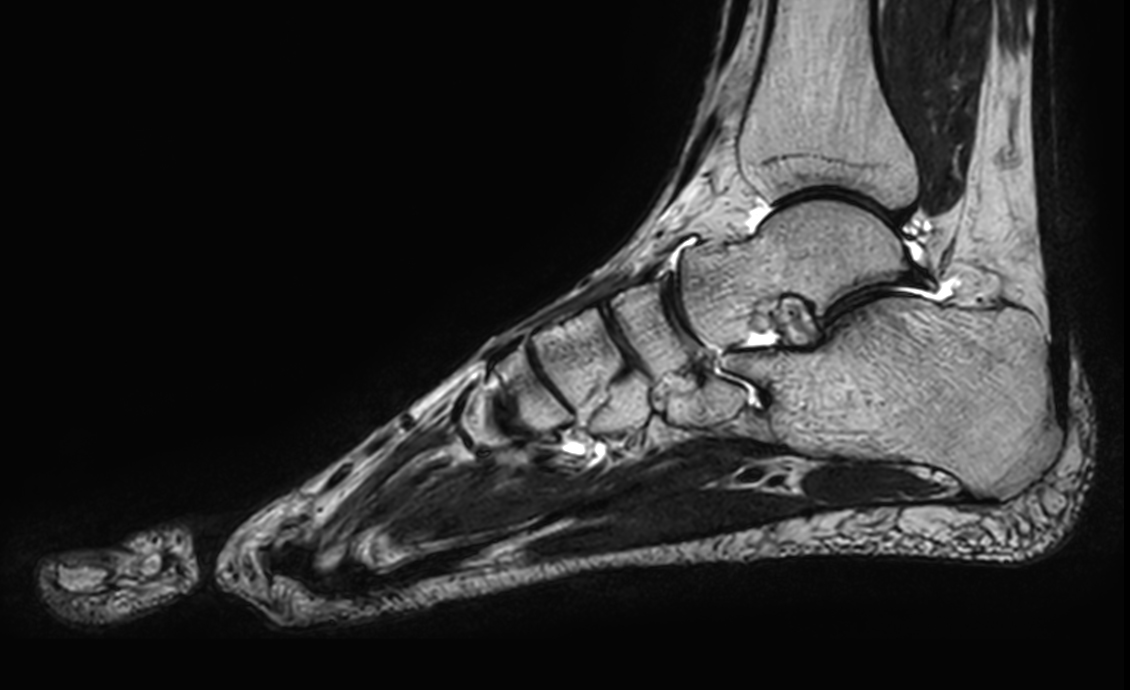

Ankle imaging with the dS 16ch FootAnkle coil

• Clinical Application